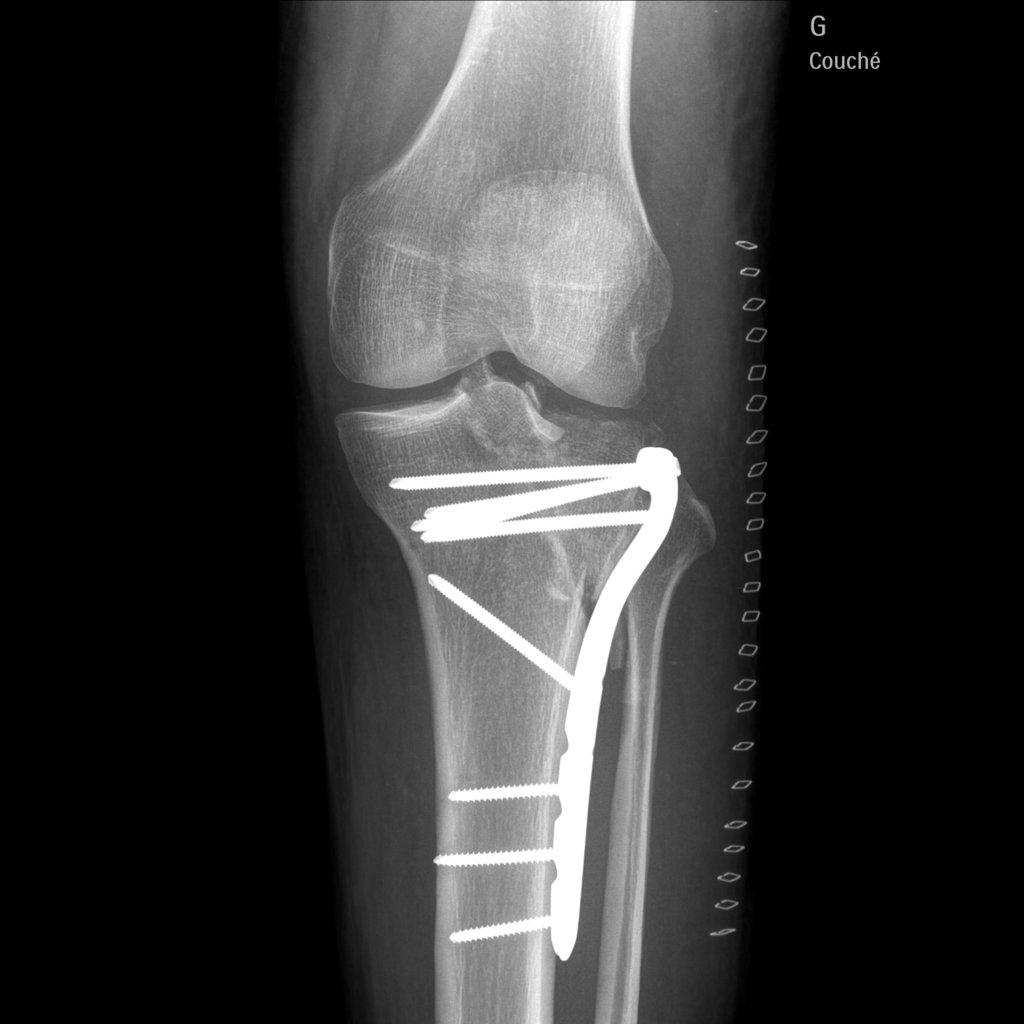

j'ai fait une sale chute en moto et j'ai du me faire opéré :( :( :( :(

j'en ai pour 3 mois sans pauser le pied a terre , et 6 mois de rééducation 1 an pour récupéré la totalité de ma jambes

1.3.46.670589.30.39.0.1.622692733605.1619697890621.1-f1.jpeg

1.3.46.670589.30.39.0.1.622692733605.1619697890648.1-f1.jpeg

Tu as dû avoir la trouille de ta vie. Un peu plus haut c'était toute l'articulation qui prenait.

Ouaouuu....ah oui c est du lourd la. Beau travail de chirurgie...a la hauteur de ce que tu sais faire de ton cote :wink: